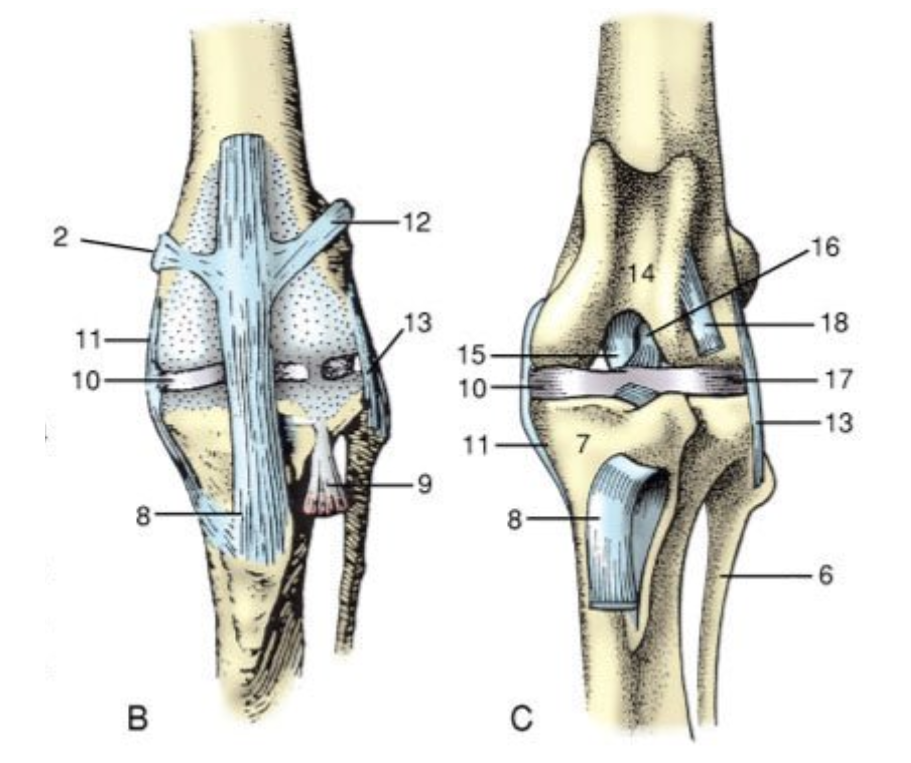

<p>1</p>

1

cranial tibial ligaments of the medial and lateral menisci

New cards

<p>2</p>

2

20

<p>3</p>

medial meniscus

21

4

medial collateral

22

<p>5</p>

5

caudal cruciate

<p>6</p>

6

24

<p>7</p>

meniscofemoral ligament

<p>8</p>

8

26

<p>9</p>

lateral meniscus

<p>15</p>

15

caudal cruciate ligament

<p>16</p>

16

cranial cruciate ligament

<p>11</p>

11

medial collateral ligament

<p>13</p>

13

lateral collateral ligament